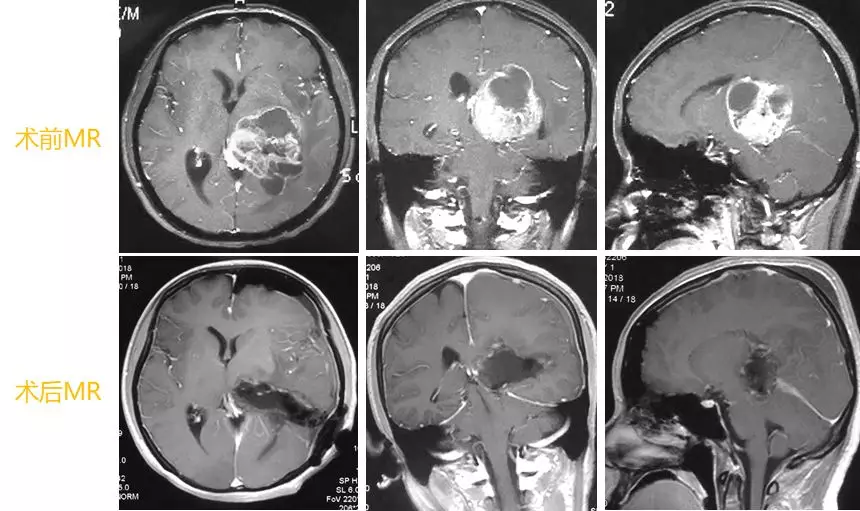

左侧丘脑肿瘤手术要点:

采用直切口,开一个较小的骨窗。

脑皮层由于肿瘤的挤压作用,向骨窗突起,电灼,切开脑皮层,进入肿瘤位置。

显微器械下,彻底切除肿瘤。

切除以后,脑组织坍陷,肿瘤切除较充分。